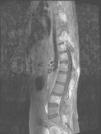

La ecografía Doppler detectó la presencia de derrame, hiperemia e hipertrofia sinovial en la rodilla izquierda. La radiografía simple del raquis mostraba la presencia de múltiples lesiones líticas vertebrales en apófisis espinosas, uniones costovertebrales y zonas posteriores de los somas vertebrales desde T10 a L4. La radiografía simple de tórax fue normal. Se completó el estudio mediante serie ósea y gammagrafía, en las que se detectó un mayor número de lesiones líticas en vértebras, costillas, pubis y radio. La tomografía computarizada permitió detectar calcificaciones adenopáticas pulmonares y sirvió como guía para la biopsia vertebral. La resonancia magnética identificó las lesiones óseas citadas, la afectación de la musculatura paravertebral y la presencia de derrame a la altura de la articulación coxofemoral izquierda (fig. 2).